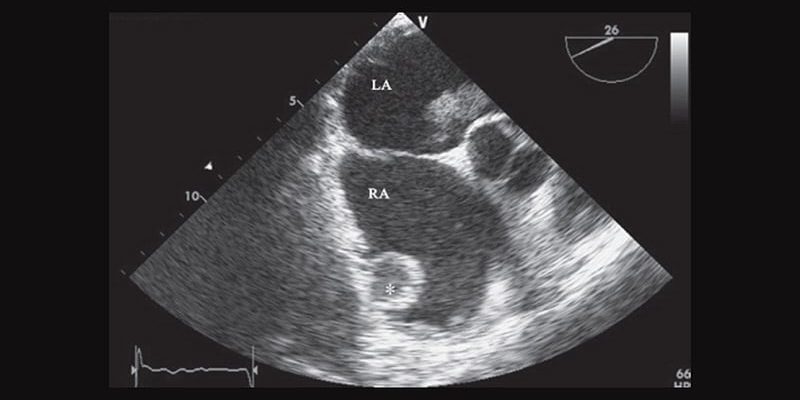

Les patients dont la CMH s’accompagnait d’un gradient de la

chambre de chasse du ventricule gauche (VG) ≥ 50 mm Hg au repos ou

lors de tests de provocation et qui, de ce fait, présentaient

les critères des recommandations internationales selon lesquels ils

pourraient bénéficier d’une réduction septale, ont été inclus dans